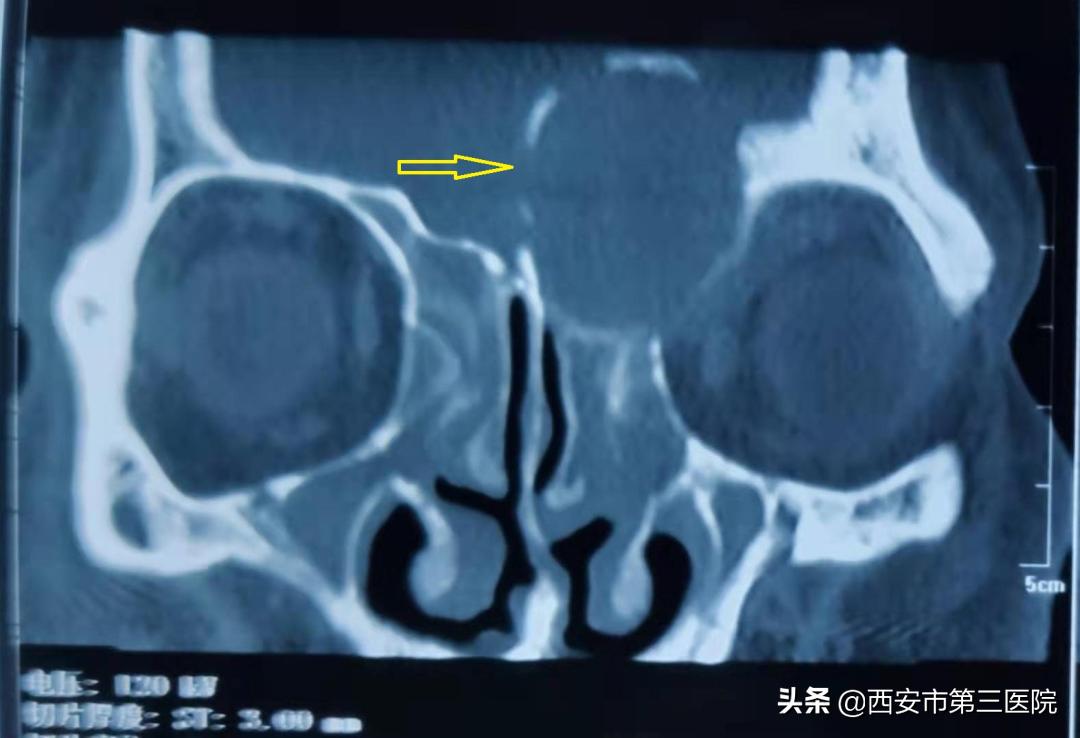

由于既往反复发作的鼻窦炎,久病成医的刘先生考虑自己可能是鼻窦炎引起的,于是便到耳鼻喉科就诊。接诊的耳鼻喉科王延辉主任仔细询问病史,经鼻窦CT检查结果显示刘先生不仅有严重的鼻窦炎,在他的左侧额窦部位还有一个“鹌鹑蛋”大小的占位影。王延辉主任当即判断,这应该是一个巨大的 额窦囊肿 。由于囊肿巨大,位于左侧颅底和眼眶,颅底向上偏移使脑组织受压移位,左侧眼眶内侧壁也受到压迫,进而导致患者眼睛肿胀,视物重影。

(术前鼻窦CT示左侧额窦区巨大占位影,脑组织受压移位,左侧眼眶受压)